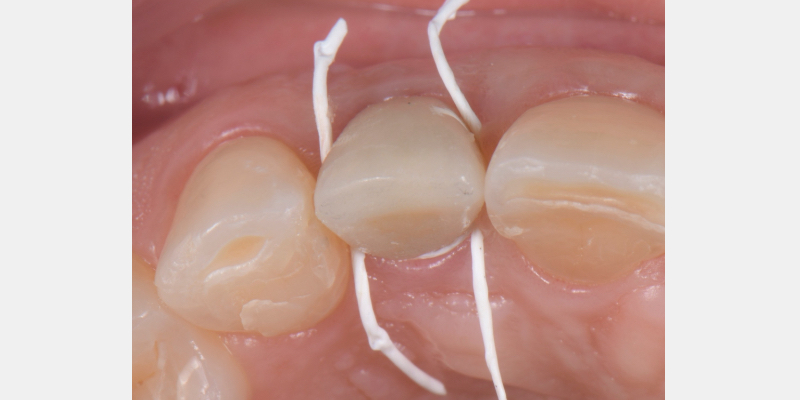

One of the most common complications with cement-retained implant restorations is inflammation around the crown. Excess cement can lead to peri-implant diseases such as peri-implant mucositis and even bone loss. A key factor to understand is the biological difference between teeth and implants — particularly the structure of the junctional epithelium and connective tissue — which makes removing residual cement around the restoration more difficult.

Here is a simple, step-by-step technique for fabricating a silicone jig to avoid excess cement in a cement-retained implant-supported restoration. It can be applied to a single crown or to an implant-supported cement-retained bridge.